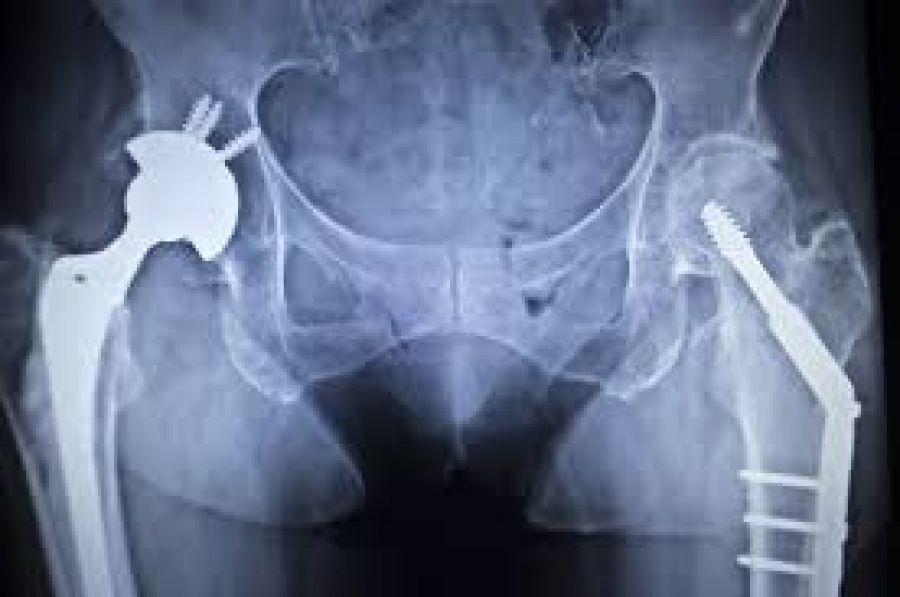

El reemplazo de la articulación implica extirpar algunas piezas de la articulación artrítica o dañada y reemplazarlas con componentes metálicos, plásticos o cerámicos que imitan los movimientos de una articulación sana. Estas cirugías son los procedimientos más comunes de reemplazo articular en Estados Unidos, país donde anualmente se hacen alrededor de 700 000 reemplazos de rodilla y 400 000 reemplazos de cadera.

La cirugía para reemplazar la cadera es un procedimiento ligeramente más directo que el reemplazo de rodilla. La razón es que la cadera es una articulación básica compuesta por una cabeza y un acetábulo. Por ello, es un proceso bastante directo en el que se fabrican y colocan las piezas para reemplazar bien la articulación. La rodilla, en cambio, es una articulación compleja que permite mayor amplitud de movimiento y más flexibilidad. Si bien la articulación de la rodilla puede reemplazarse con éxito, la técnica para hacerlo es más complicada y generalmente requiere mayor tiempo de recuperación que la cirugía de la cadera.